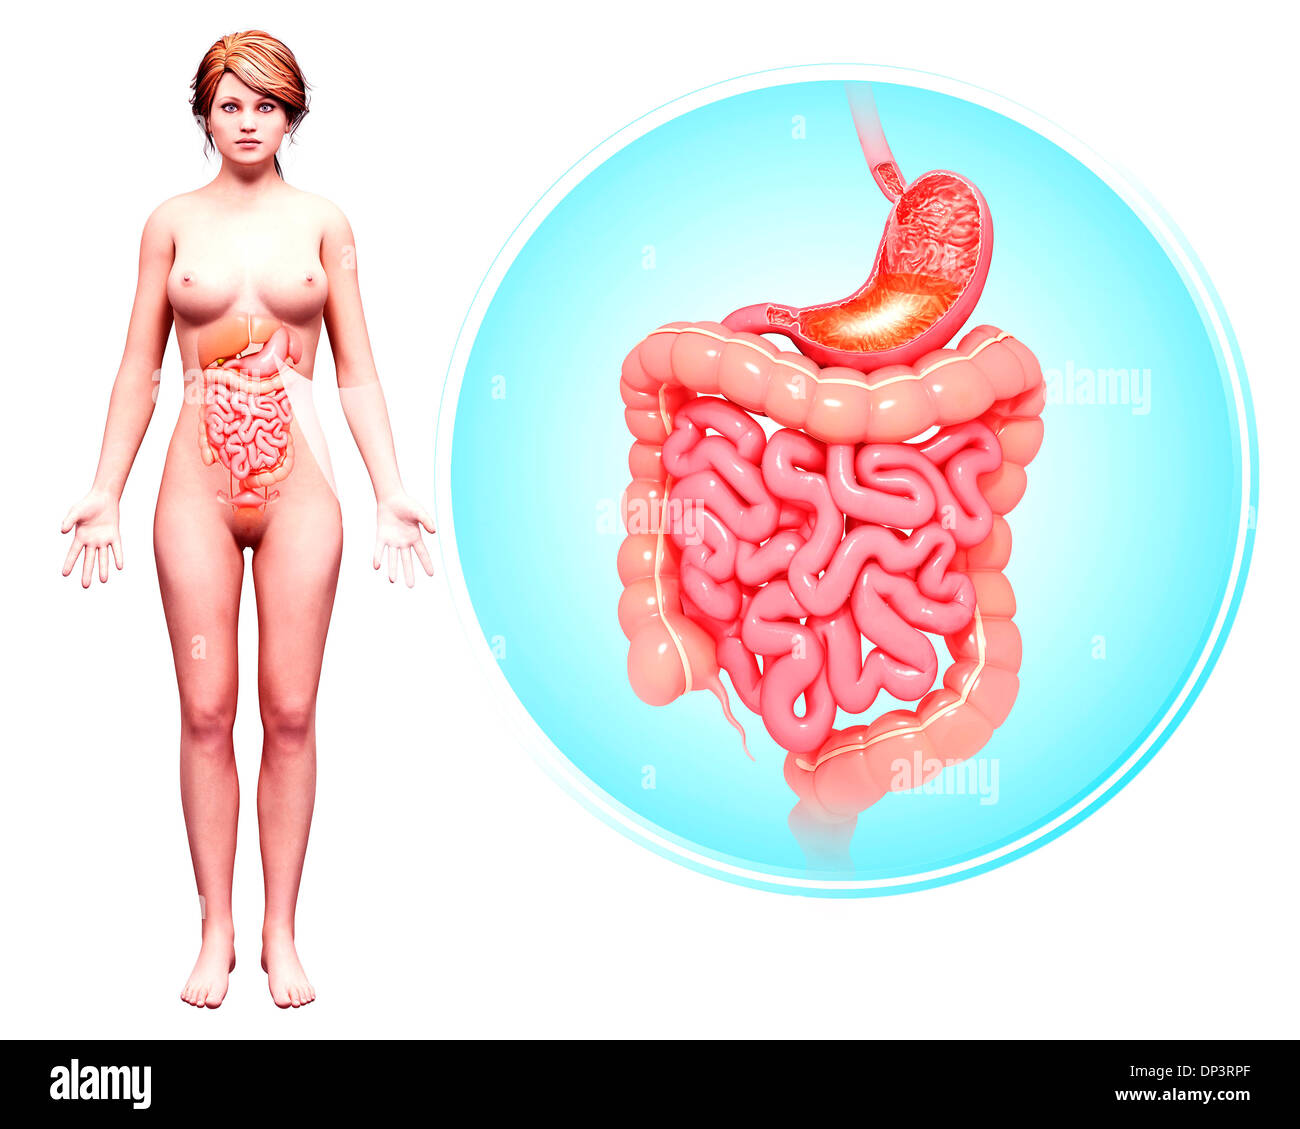

Système digestif humain, artwork Banque D'Imageshttps://www.alamyimages.fr/image-license-details/?v=1https://www.alamyimages.fr/systeme-digestif-humain-artwork-image65238160.html

Système digestif humain, artwork Banque D'Imageshttps://www.alamyimages.fr/image-license-details/?v=1https://www.alamyimages.fr/systeme-digestif-humain-artwork-image65238160.htmlRFDP3RX8–Système digestif humain, artwork

Système digestif humain, artwork Banque D'Imageshttps://www.alamyimages.fr/image-license-details/?v=1https://www.alamyimages.fr/systeme-digestif-humain-artwork-image65238055.html

Système digestif humain, artwork Banque D'Imageshttps://www.alamyimages.fr/image-license-details/?v=1https://www.alamyimages.fr/systeme-digestif-humain-artwork-image65238055.htmlRFDP3RPF–Système digestif humain, artwork